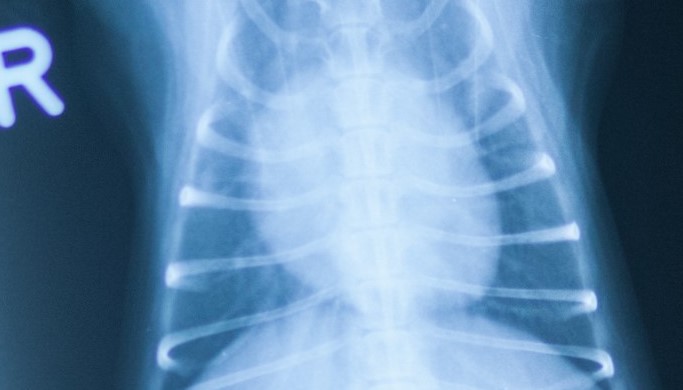

Die Untersuchung und Behandlung von Patienten mit Herzerkrankungen sind ein Spezialgebiet unserer Praxis. Zur Herzuntersuchung stehen neben dem modernen Ultraschallgerät auch EKG, Blutdruckmessung und Röntgen zur Verfügung. Erfahrung und kontinuierliche Fortbildung ermöglichen Diagnostik und Therapie auf höchstem Niveau.